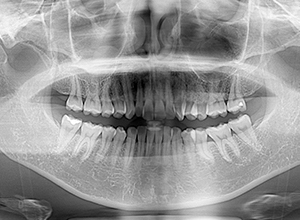

X-Ray

X-Ray所見

パノラマ所見 左右上5、左下5に歯根の湾曲が認められた。上下顎左右側8は抜去済みであった。